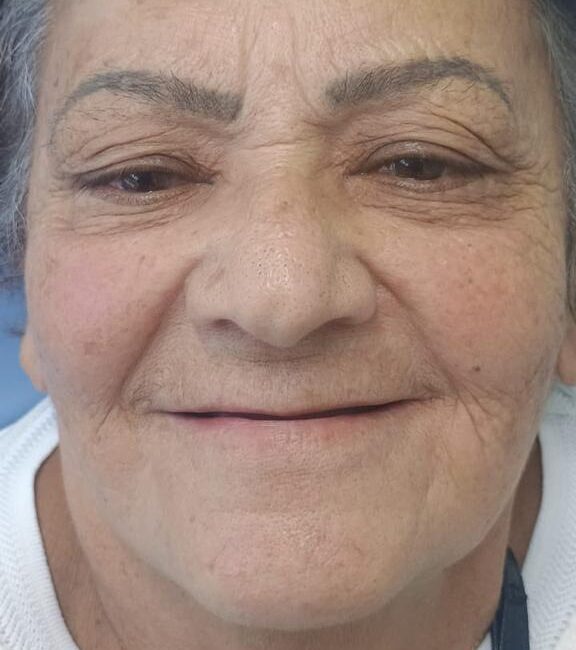

É uma técnica avançada de reabilitação oral que utiliza implantes zigomáticos para suportar próteses dentárias. Indicada para pacientes que apresentam atrofia severa do osso maxilar, tornando a colocação de implantes convencionais inviável.

O protocolo dental zigomático é uma técnica avançada de reabilitação oral que utiliza implantes zigomáticos para suportar próteses dentárias. Essa abordagem é especialmente indicada para pacientes que apresentam atrofia severa do osso maxilar, tornando a colocação de implantes convencionais inviável.

– Pacientes com atrofia severa do osso maxilar.